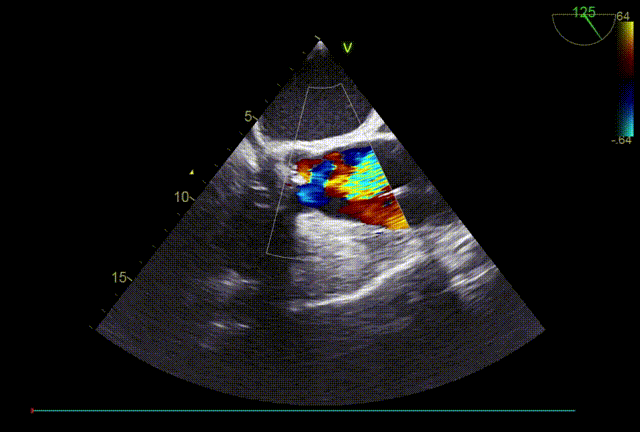

TTE